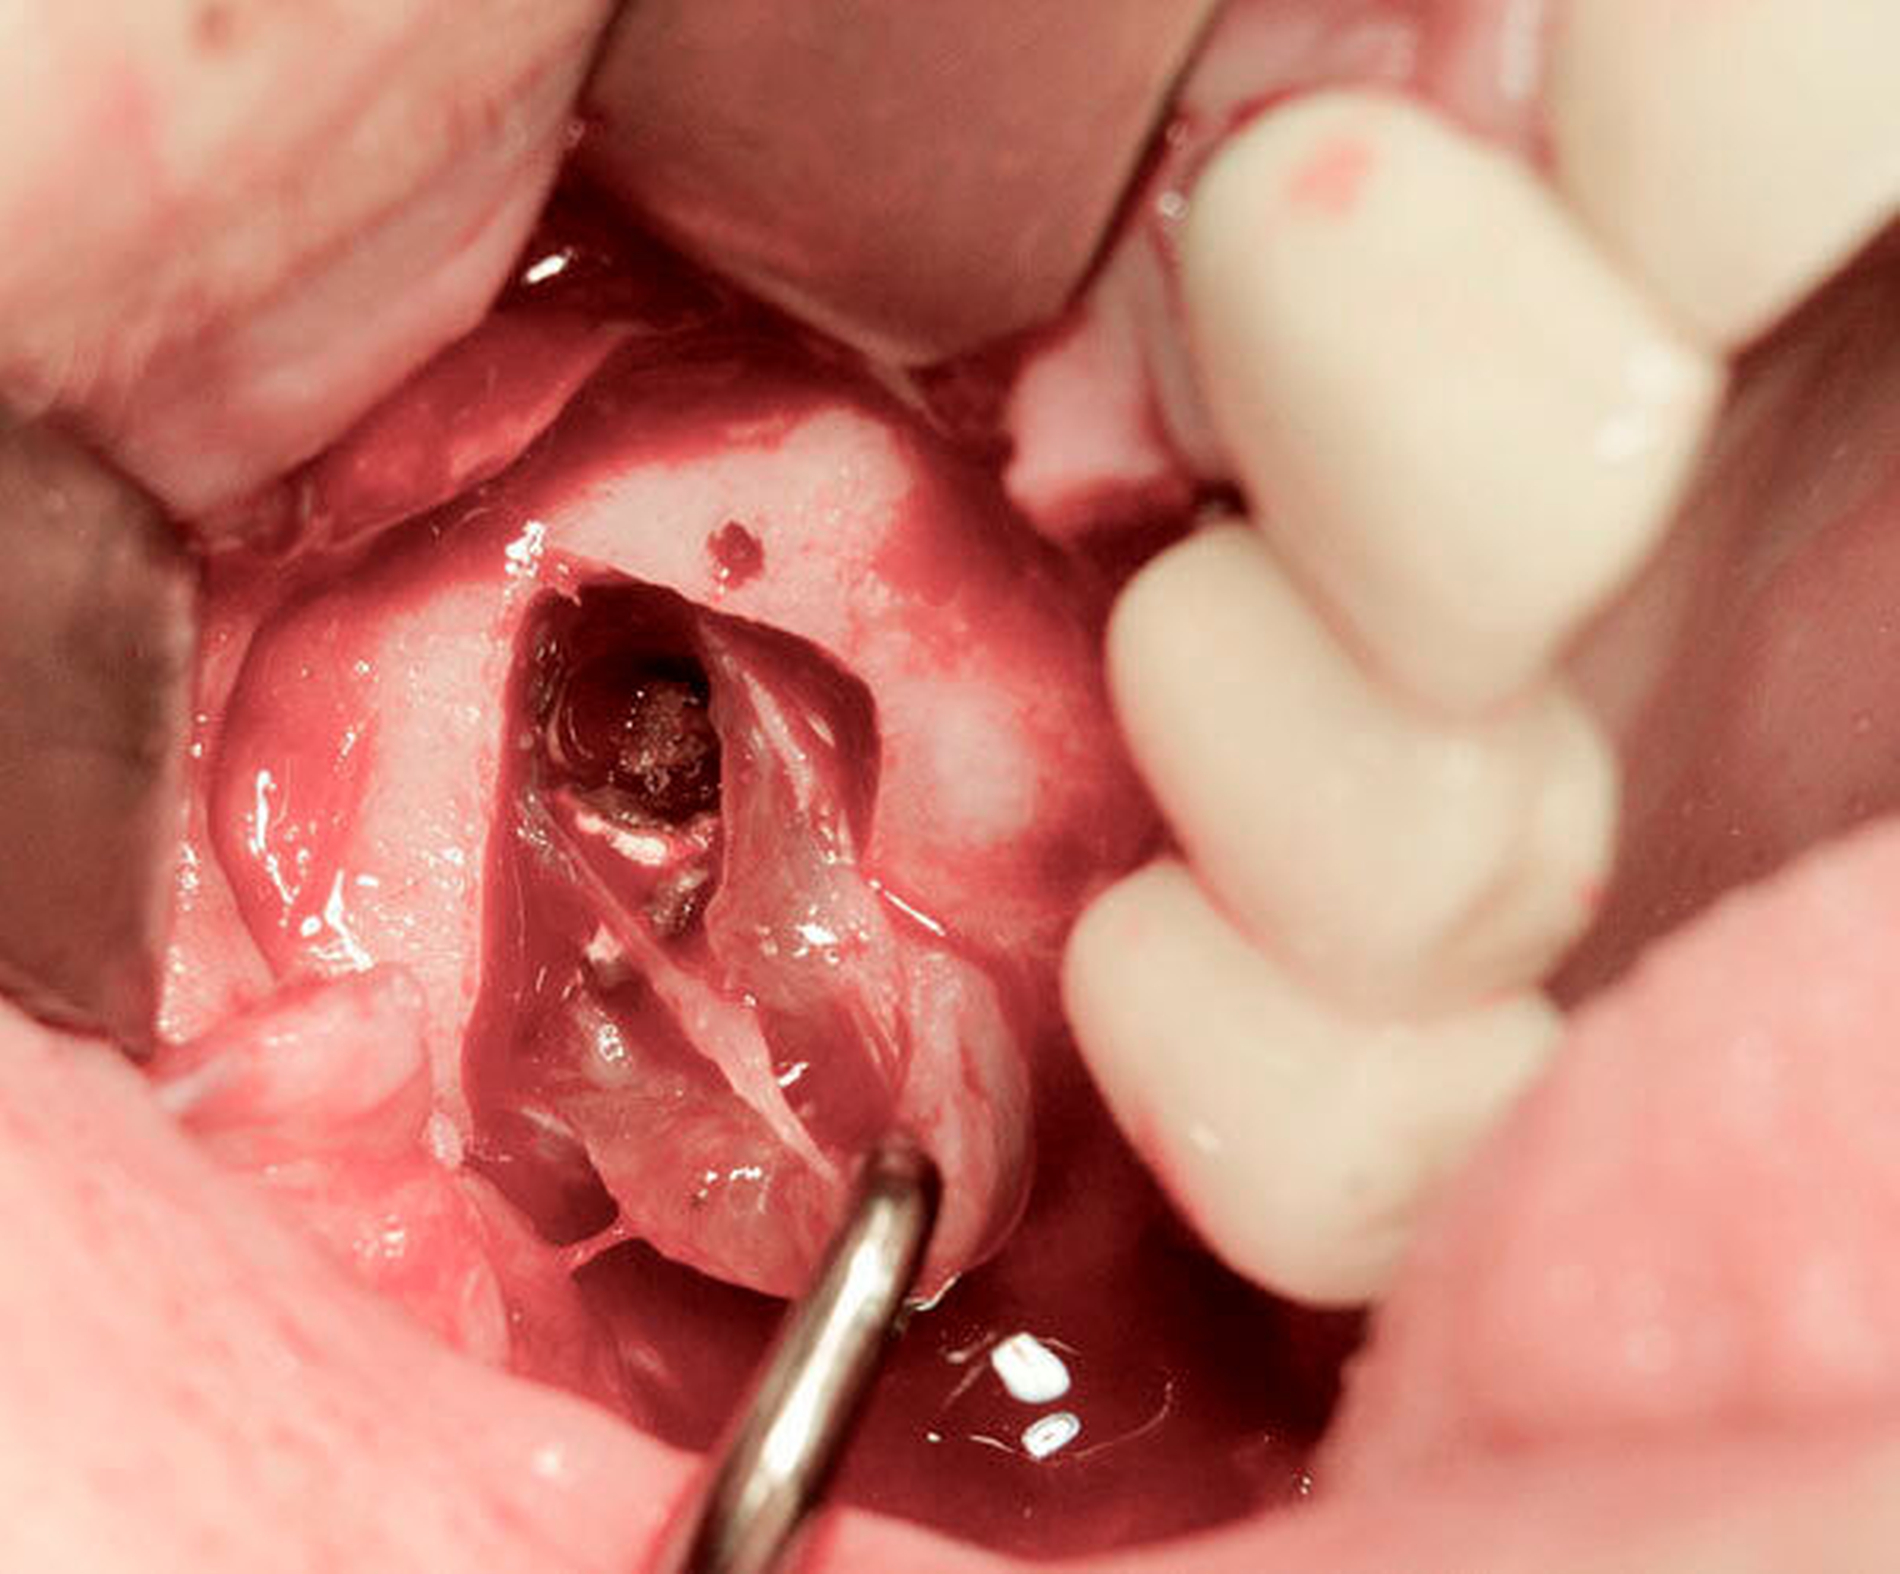

Der luxierte Zahn konnte mittels Extraktionszange gefasst werden. Es bestand eine Mund-Antrum-Verbindung, die plastisch verschlossen wurde (Abbildungen 6 und 7). Postoperativ war die Patientin weiterhin beschwerdefrei.

Im Fall des luxierten Implantats wurde in Intubationsnarkose ein Knochendeckel angelegt (Abbildung 8) und das Implantat über diesen Zugang extrahiert (Abbildungen 9 und 10).

Klinisch zeigten sich ausgeprägte polypöse Schleimhautveränderungen. Die ehemalige Insertionsstelle des Implantats war vollständig verschlossen. Nach Entfernung des Implantats, Reposition und Fixation des Knochendeckels wurde der Mukoperiostlappen in Ursprungsposition vernäht.